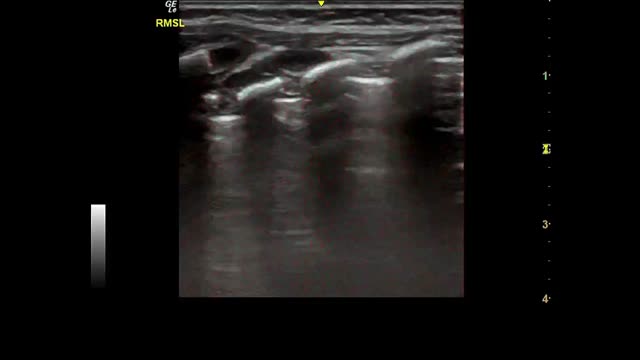

Most of the studies under analysis had LU findings in common in the presence of SARS-CoV-2 infection. The most common finding was B lines, which had very distinct characteristics, 34 of which reported focal, diffuse and confluent B lines.12,15,18,19,25,26,27,29,30,31,32–35,38,62,67,68,70,72–74,77–88 Twenty-nine studies described consolidations of different types: small, large, linear, subpleural, multifocal and translobar,12,15,18,19,25,26,27,29,30,33,35,38,62,63,67,68,70,72,73,75,78–80,82–85,87,89 associated with white lung12,30 and with air bronchograms18,38. Nineteen studies described pleural irregularities,12,15,18,26,27,30,32,33,35,62,70,72,77,79,80,82,84,85,89 and 19 reported pleural and subpleural line alterations, such as thickening or shred sign.18,19,26,29,31,32,34,38,62,67,70,72,73,75,77,80,85 Ten studies referred to pleural effusion,38,62,67,70,72,75,77,82–84 8 reported bilateral findings15,34,63,79,82,86,87,88 and 3 revealed preponderance of compromise in posterior areas.79,80,89 Three studies associated appearance of A lines during recovery 35,67,80 and most of the papers reported the LU role in the serial evaluation of patients with COVID-19.27,29,30,33,35,67,68,70,71,72,74,75–77,80

Some studies reported radiological findings agreement between LU and HCRT.15,18,25,27,29,32,33,35,38,62,63,65,68,70,78,79,83,84,87,89 The main HCRT findings were ground glass opacities, “crazy-paving” pattern, consolidations, pulmonary infiltrates and pleural thickening as well as interlobular septal thickening.18,29,32,33,35,38,62,65,68,70,73,75,78,79,81,83–85,87,89 When comparing thorax HRCT features with those of LU in pneumonia resulting from COVID-19 the findings included (i) correlation of ground glass opacity with B lines (multifocal, discrete or confluent); (ii) presence of thickened pleura in HRCT with thickening of the pleural line in LU; (iii) pulmonary infiltrates as confluent B lines in LU; (iv) pulmonary consolidation in both techniques20 The finding “white lung” was also described as ground glass opacity in HRCT.15,18,26,27,38,62,78,87

Fig. 2 shows the main findings of the LU imaging described in the study.